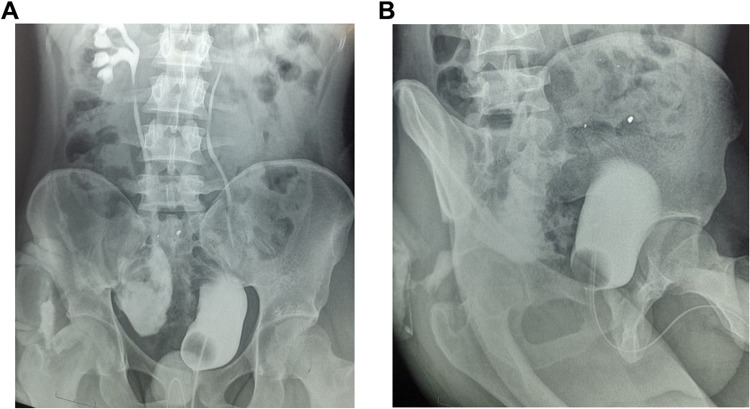

泌尿外科最具挑战性的工作之一是恢复长缺损输尿管的通畅。在某些情况下,利用自身组织或膀胱对输尿管进行整形手术可能并不可行。在这种情况下,阑尾输尿管成形术等替代方案可能是有希望的解决方案。输尿管损伤有多种病因,其中一些是继发于手术过程中无意造成的输尿管创伤。一半以上的输尿管损伤在首次开腹手术中未被发现。大面积输尿管损伤很难修复,即使采用多种外科技术也是如此。阑尾输尿管成形术的优势在于输尿管置换技术简单,在手术失败时不会影响其他替代方案。本病例报告的是一名腹部枪伤的年轻成人,其右输尿管远端三分之一处组织严重缺失。我们成功实施了阑尾尿道成形术。经过一年的门诊随访,患者病情保持稳定。

One of the most challenging aspects of urology is restoring patency to ureters with long defects. In certain cases, it may not be feasible to perform plastic surgery on the ureter with its own tissue or bladder. In such instances, alternative solution like appendicular ureteroplasty may be promising solution. Ureteral injuries have several etiologies, some of them are secondary to unintentional ureteral trauma during surgery. More than half of these injuries are unrecognized during the first laparotomy. Extensive ureteral injuries are difficult to repair, even with application of several types of surgical techniques. The advantage of appendicular ureteroplasty is the simplicity of the ureteral replacement technique without compromising other substitution options in case of failure. This is a case report of a young adult with abdominal gunshot injuries, with significant loss of tissues located to distal third of the right ureter. The appendicular urethroplasty was successfully performed. The patient remained stable after one year of out follow-up as an outpatient.